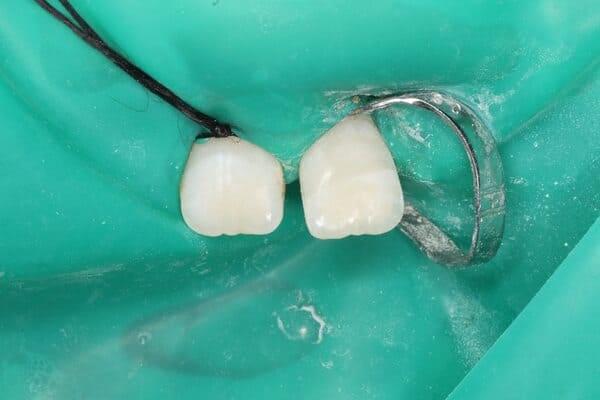

1. Знайдіть зуб або його уламок.

2. Тримайте правильно: Беріть зуб лише за коронкову частину (білу верхівку). Не торкайтеся кореня!

3. ​Зберігання: Не мийте зуб водою і не тріть його. Помістіть його у молоко або фізіологічний розчин. Це критично важливо для збереження життєздатності клітин кореня.

1. Якщо відколовся невеликий шматочок — знайдіть його і покладіть у молоко/фізрозчин.